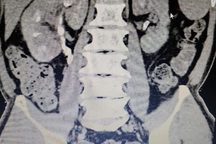

Qua thăm khám, bệnh nhân được chẩn đoán sỏi san hô thận trái, sỏi niệu quản trái trên nền tiểu đường, tăng huyết áp. Đáng chú ý, các bác sĩ phát hiện bệnh nhân mắc một tình trạng hiếm gặp: Thận móng ngựa.

Theo bác sĩ Nguyễn Hồng Long - Khoa Ngoại tổng hợp, Bệnh viện Hữu Nghị, ở người bình thường hai thận sẽ nằm hai bên cạnh cột sống và tách rời nhau. Tuy nhiên ở bệnh nhân bị thận móng ngựa, hai thận sẽ dính vào nhau thành một khối vắt ngang cột sống. Vì thế sẽ dẫn đến các bất thường giải phẫu và khi mổ sẽ dễ gặp tai biến và nguy cơ phải cắt toàn bộ thận là rất cao.

Với trường hợp của bệnh nhân V., kíp phẫu thuật đã mổ nội soi lấy sỏi thận, đồng thời tán sỏi niệu quản trái nội soi ngược dòng. Nhờ triển khai đồng bộ các phương pháp tiên tiến nhất nên bệnh nhân đã được can thiệp xâm lấn tối thiểu nhất. Ca mổ đã thành công sau 2 giờ phẫu thuật.